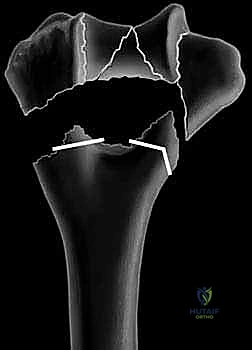

يُعد كسر عظم العضد البعيد، وتحديداً تلك الكسور التي تمتد لتشمل الجزء السطحي والمفصلي (مثل الكسور فوق اللقمية Supracondylar والكسور بين اللقمتين Intercondylar)، من أعقد الإصابات في مجال جراحة العظام والكسور. تتطلب هذه الحالات خبرة جراحية استثنائية، وفهماً عميقاً للميكانيكا الحيوية للمفصل، ودقة متناهية في التشخيص والتخطيط الجراحي.

تحدث هذه الكسور في الجزء السفلي من عظم العضد، وهو العظم الطويل في الذراع، وتحديداً في النقطة التي يلتقي فيها مع عظام الساعد (الكعبرة والزند) لتشكيل مفصل الكوع. تكمن صعوبة هذه الإصابات في التشريح المعقد ثلاثي الأبعاد للمفصل، ورقة العظم القشري في هذه المنطقة (خاصة في الحفرة الزندية والإكليلية)، ووجود شبكة معقدة من التراكيب العصبية والوعائية الحيوية التي تمر على بعد مليمترات قليلة من العظم.

إن التفتت الشديد الذي غالباً ما يواجهه الجراح، خاصة في منطقة ما بين اللقمتين (Intercondylar region)، هو السمة المهيمنة التي تعقد استراتيجية التثبيت الداخلي. يتطلب التعامل مع هذه الحالات تخطيطاً دقيقاً باستخدام الأشعة المقطعية ثلاثية الأبعاد، وتنفيذاً جراحياً محترفاً، وهو ما يبرع فيه الأستاذ الدكتور محمد هطيف في مركزه المتخصص بصنعاء.

4. الرد المفتوح (Open Reduction) - إعادة تجميع القطع

هنا تبدأ المرحلة الهندسية الدقيقة. يقوم الجراح بتنظيف موقع الكسر من الجلطات الدموية والأنسجة الميتة. ثم يبدأ في إعادة تجميع الشظايا العظمية (كأنها قطع أحجية/بازل). يتم التركيز أولاً على إعادة بناء السطح المفصلي (البكرة والرأس) بدقة تشريحية تامة بنسبة 100% لتجنب خشونة المفصل مستقبلاً. يتم تثبيت هذه القطع مؤقتاً باستخدام أسلاك كيرشنر (K-wires) الدقيقة.